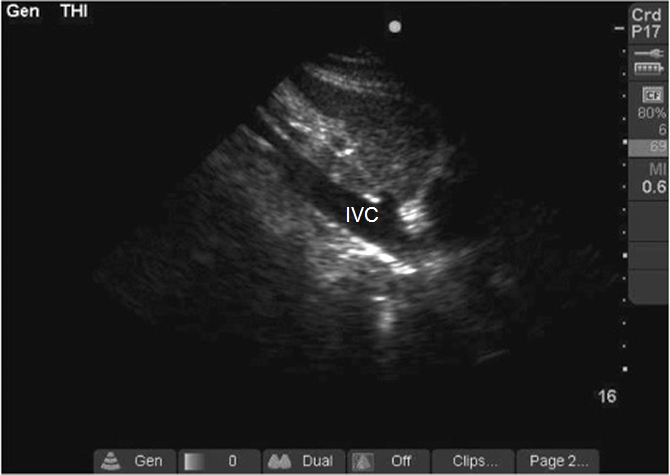

Case 7-5. Inferior Vena Cava Long-axis View

Video 7-5A. Small diameter inferior vena cava (IVC) in longitudinal axis.

Video 7-5B. Large IVC without respiratory variation.

Video 7-5C. Problem with the measurement that occurs in patients with translational artifact due to movement of the IVC in and out of the tomographic plane. If the examiner is trying to reliably measure a 12% variation of IVC size as a determinant of preload sensitivity, true respiratory variation may be difficult to distinguish from translational artifact. Examination of variation in superior vena cava size with transesophageal echocardiography is an effective alternative. Respirophasic diameter variation of the IVC has utility in determination of preload sensitivity, if the patient is on mechanical ventilatory support without spontaneous respiratory effort. The diameter alone may have some value in this determination, but only at the extremes of size.